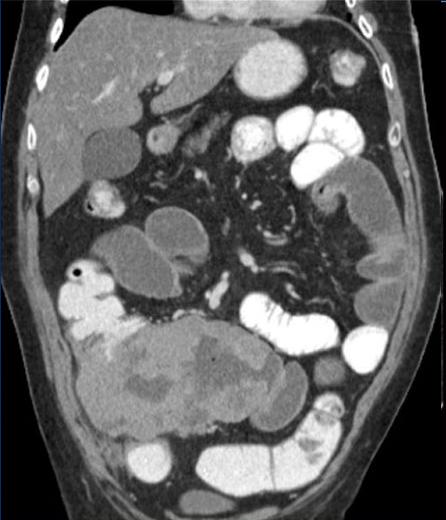

| Extension loco regionale

d'une lymphome T dans une maladie coeliaque de

l'intestin . ( la paroi de l'intestin dans ce cas

est perdre de villocite etendue ) . Image TDM ,

coupe frontale ( coronale ) |